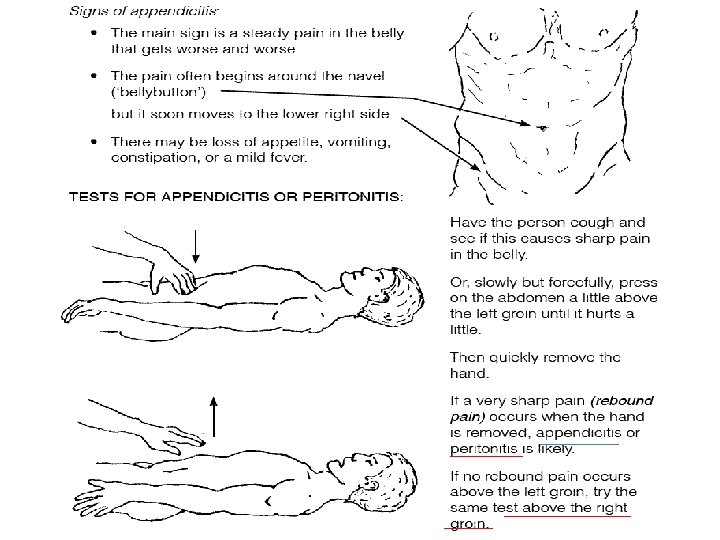

KLINIKA: • DHIMBJA: Fillimisht e moderuar ne forme kolike ne regionin periumbilikal, me pas shnderrohet ne dhimbje te qendrueshme e zhvendosur ne kuadrantin inferior dexter.

NE PALPIM: - Mac Burney (+): 1/3 e poshtme e distances prej umbilikusit ne spina iliake anteriosuperior

- Rebound (+): dhimbja e madhe gjate heqjes se menjehershme te dores palpuese ne kuadrantin inferior dexter. - Defans (+): mbrojtje muskulare ne kuadrantin inferior dexter. - Temperature: subfebrile- e larte, e shoqeruar me frisone +/- te vjella - Leukocitoze - Crregullime te tranzitit: konstipacion, rralle diare.